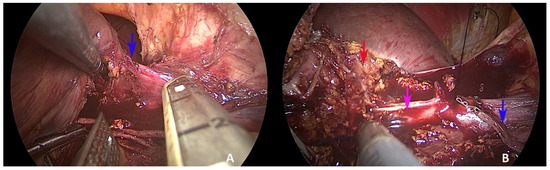

Laparoscopic Resection of Synchronous Liver Metastasis Involving the Left Hepatic Vein and the Common Trunk Bifurcation: A Strategy of Parenchyma-Sparing Resection with Left Sectionectomy and 4a Subsegmentectomy by Arantius Approach

2. Case Presentation